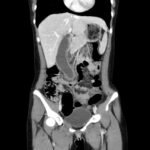

An 18-year-old female presented to the emergency department (ED) with two days of right lower quadrant pain and associated nausea and emesis. After relevant information was gathered and with physical exam findings of a tender right lower quadrant, positive psoas sign, positive Rovsing sign, and pain with right heel tap, the patient was presumed to have appendicitis. However, imaging contradicted the initial leading diagnosis and revealed a markedly distended, hydropic gallbladder with its tip near the umbilicus. Findings of the distended gallbladder with marked wall thickening and pericholecystic fat stranding and edema confirmed acute cholecystitis, and the patient was taken by general surgery for cholecystectomy. Together, this unusual presentation and this unexpected diagnosis shine light upon another facet of the hydropic gallbladder while also serving as a salient reminder to contemplate a broad differential regardless of seemingly classic presentations of illnesses.